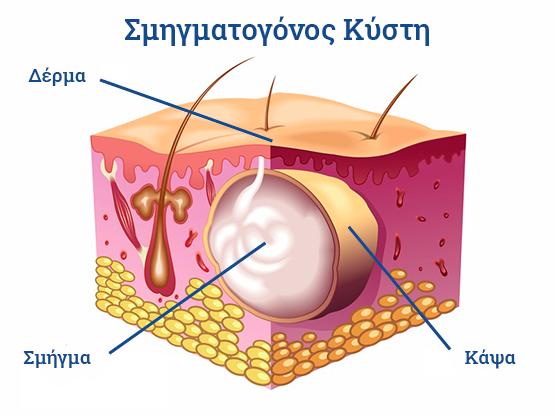

- Σμηγματογόνος κύστης θεραπεία

- Σμηγματογόνος κύστης θεραπεία

Ο Γενικός Χειρουργός Λιάγκος Γεώργιος MD PhD εκτελεί τις επεμβάσεις Λαπαροσκοπικά, Ενδοσκοπικά, Ανοιχτά Ελάχιστα Επεμβατικά και με Laser. Η θεραπεία εξατομικεύεται σε κάθε ασθενή ανάλογα με τις ανάγκες του. Αναλαμβάνει περιπτώσεις όπως κήλες και κοιλιοκήλες (αντιμετώπιση βουβωνοκήλης, αντιμετώπιση ομφαλοκήλης, θεραπεία επιγαστρικής κήλης, κήλη των αθλητών (Σύνδρομο κοιλιακών προσαγωγών), αντιμετώπιση μετεγχειρητικής κήλης, θεραπεία Μηροκήλης), πέτρες στη χοληδόχο κύστη, λαπαροσκοπική χολοκυστεκτομή, αντιμετώπιση Κύστη Κόκκυγος με λέιζερ (laser), παθήσεις πρωκτού, χειρουργική laser σύγχρονων κυκλικών ινών (αιμορροΐδες αντιμετώπιση, θεραπεία αιμορροϊδων με laser (LHP), αφαίρεση αιμορροΐδων με υπερήχους (HALL-RAR), χωρίς Χειρουργείο με ελαστικούς δακτυλίους (Τεχνική BARON-RBL), θεραπεία ραγάδας πρωκτού (Ραγάδα δακτυλίου), θεραπεία περιεδρικού συριγγίου, θεραπεία περιεδρικού αποστήματος, κονδυλώματα πρωκτού Θεραπεία, δερματικό ράκος (Skin tag) εκτομή, αντιμετώπιση Kνησμού, καρκίνος πρωκτού θεραπεία), παθήσεις Δέρματος, χειρουργική με laser CO2, αφαίρεση μορφωμάτων δέρματος - βιοψίες, αφαίρεση ελιάς (Σπίλου), σμηγματογόνος κύστης θεραπεία, αφαίρεση λιπώματος, είσφρυση όνυχος χειρουργείο, καρκίνος δέρματος θεραπεία, οξεία σκωληκοειδίτιδα, παθήσεις Λεπτού και Παχέος Εντέρου, ειλεός λεπτού εντέρου, εκκολπωμάτωση (Εκκολπωματίτιδα) σιγμοειδούς, καρκίνος παχέος εντέου, κολοστομίες, port χημειοθεραπείας κ.α.

Ο Γενικός Χειρουργός Λιάγκος Γεώργιος MD PhD εκτελεί τις επεμβάσεις Λαπαροσκοπικά, Ενδοσκοπικά, Ανοιχτά Ελάχιστα Επεμβατικά και με Laser. Η θεραπεία εξατομικεύεται σε κάθε ασθενή ανάλογα με τις ανάγκες του. Αναλαμβάνει περιπτώσεις όπως κήλες και κοιλιοκήλες (αντιμετώπιση βουβωνοκήλης, αντιμετώπιση ομφαλοκήλης, θεραπεία επιγαστρικής κήλης, κήλη των αθλητών (Σύνδρομο κοιλιακών προσαγωγών), αντιμετώπιση μετεγχειρητικής κήλης, θεραπεία Μηροκήλης), πέτρες στη χοληδόχο κύστη, λαπαροσκοπική χολοκυστεκτομή, αντιμετώπιση Κύστη Κόκκυγος με λέιζερ (laser), παθήσεις πρωκτού, χειρουργική laser σύγχρονων κυκλικών ινών (αιμορροΐδες αντιμετώπιση, θεραπεία αιμορροϊδων με laser (LHP), αφαίρεση αιμορροΐδων με υπερήχους (HALL-RAR), χωρίς Χειρουργείο με ελαστικούς δακτυλίους (Τεχνική BARON-RBL), θεραπεία ραγάδας πρωκτού (Ραγάδα δακτυλίου), θεραπεία περιεδρικού συριγγίου, θεραπεία περιεδρικού αποστήματος, κονδυλώματα πρωκτού Θεραπεία, δερματικό ράκος (Skin tag) εκτομή, αντιμετώπιση Kνησμού, καρκίνος πρωκτού θεραπεία), παθήσεις Δέρματος, χειρουργική με laser CO2, αφαίρεση μορφωμάτων δέρματος - βιοψίες, αφαίρεση ελιάς (Σπίλου), σμηγματογόνος κύστης θεραπεία, αφαίρεση λιπώματος, είσφρυση όνυχος χειρουργείο, καρκίνος δέρματος θεραπεία, οξεία σκωληκοειδίτιδα, παθήσεις Λεπτού και Παχέος Εντέρου, ειλεός λεπτού εντέρου, εκκολπωμάτωση (Εκκολπωματίτιδα) σιγμοειδούς, καρκίνος παχέος εντέου, κολοστομίες, port χημειοθεραπείας κ.α.